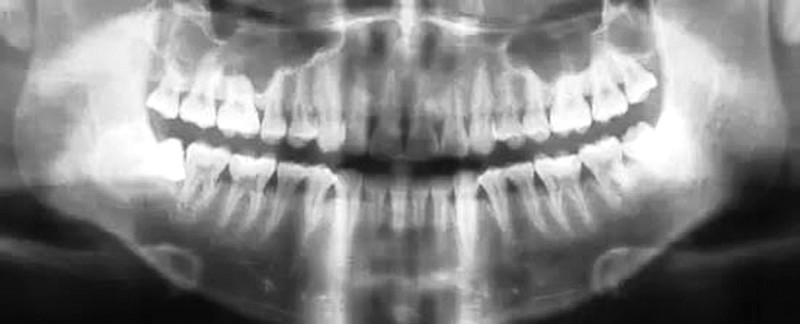

面对消费者普遍存在的疑惑与犹豫,记者在中国口腔科普公益联盟线下活动中采访到北京德医口腔诊所得李牧政主任,他表示牙齿健康不能忽视,智齿问题在学界也存在争议,有些人可能智齿一萌出就开始发炎疼痛,而有的人却能顺利生长不受影响。消费者可以首先通过三个方式对自己智齿进行一个初步判断,第一是记录智齿是否经常发炎,影响日常生活;第二是观察智齿生长位置是否正常,邻牙有没有出现病变、倾斜的情况;第三是留意智齿是否影响咬合,对于日常咀嚼食物是否有帮助。“当发现有这三种情况发生时,应该及时就诊,拍个全景牙片,进行专业的诊断。”